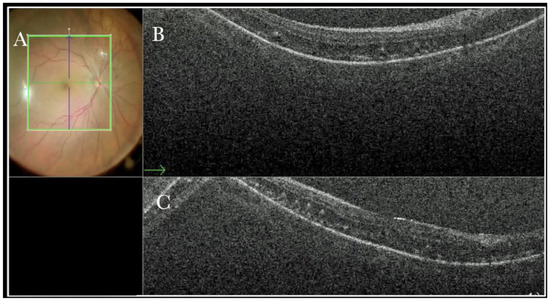

Figure 13.

(A) Microscope view of the macular area in a case of retinal detachment. The retina is flat under perfluorocarbon liquid (PFCL). The surgeon was considering at this point whether to perform a peeling of the inner limiting membrane (ILM) to prevent the formation of an epiretinal membrane (ERM). (The green box indicates the field-of-view of the OCT scan, the green and blue lines within the green box show the vertical and horizontal scan planes). (B) The intraoperative optical coherence tomography (i-OCT) B horizontal scan shows the thinning of the fovea and indicates the surgeon had a high risk of inducing a full-thickness macular hole (FTMH) if performing the ILM peeling. (White borders of circle) a decision not to peel was taken after looking at the i-OCT scan. (C) En-face view of the macular area in a case of retinal detachment. (The green line represents the scan plane).

Furthermore, the i-OCT view helped to study the anatomy of the retina when it appeared fully reattached through the microscope (Figure 14). A series of microfolds were observed in the external layers.

Figure 14.

(A) Microscope view of the macular area in a case of retinal detachment. The retina is flat under perfluorocarbon liquid (PFCL). (The green box indicates the field-of-view of the OCT scan, the green and blue lines within the green box show the vertical and horizontal scan planes). (B) The intraoperative optical coherence tomography (i-OCT) B horizontal (green arrow) scan shows that the retina is flat. The outer layers are slightly edematous and present microfolds. (C) i-OCT B vertical scan shows that the retina is flat. The outer layers are slightly edematous and present microfolds.